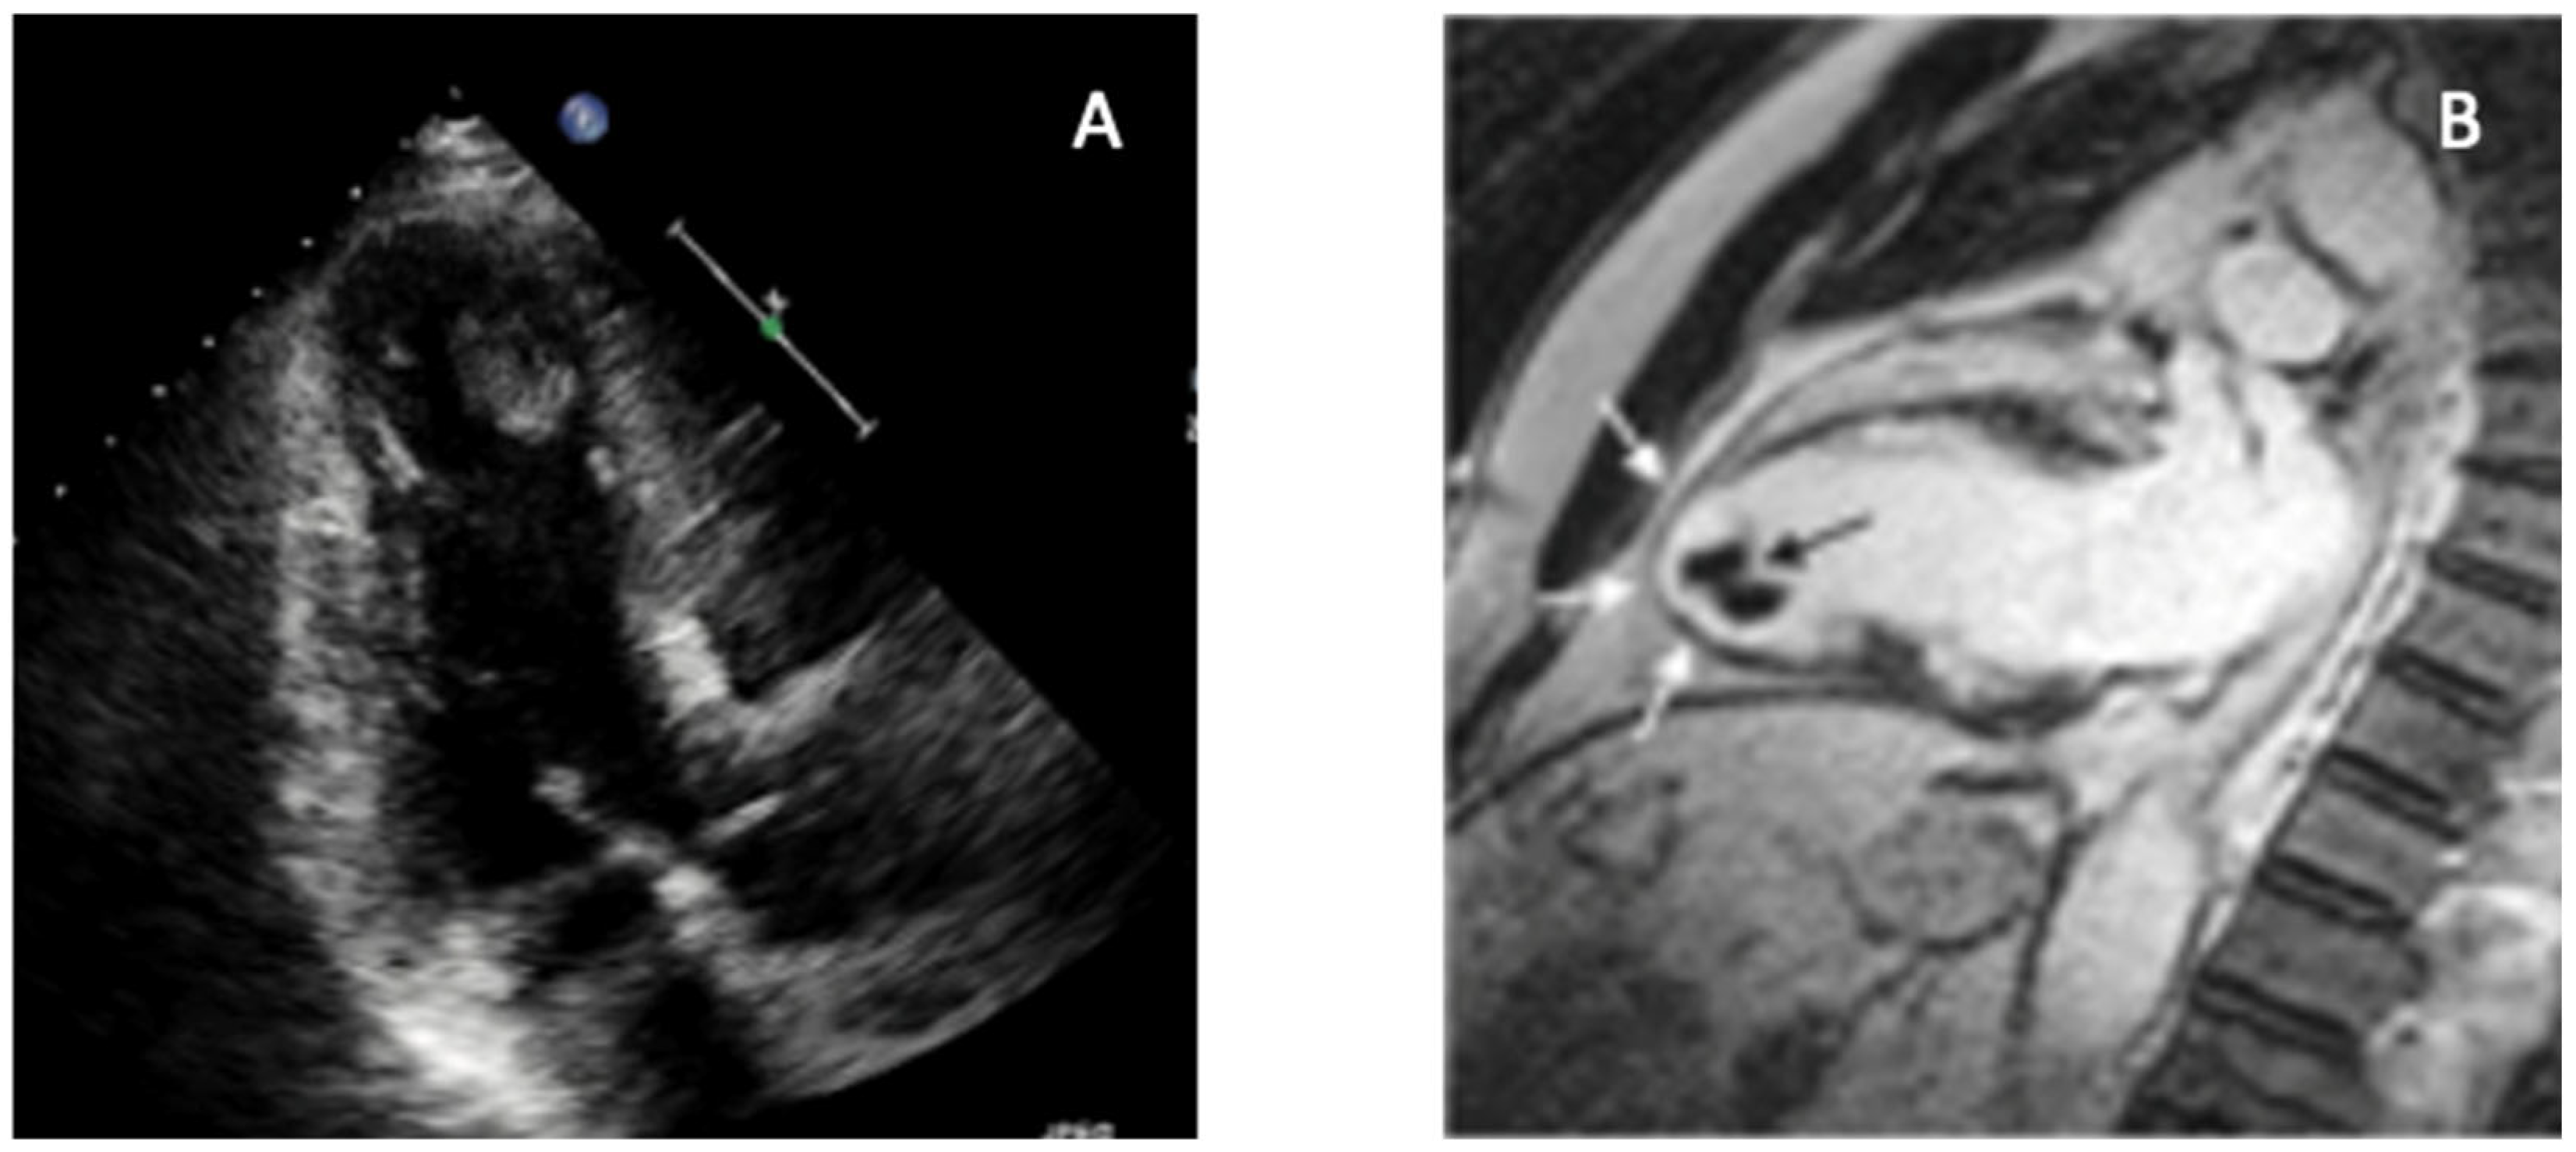

4.4. Endomyocardial Fibrosis/Hypereosinophilic Syndrome

| Endomyocardial Fibrosis | Apical obliteration; restrictive filling; mural thrombus common; thickened endocardium | Marked apical strain reduction; basal-apical gradient reversed | Subendocardial LGE (“V-sign”); apical fibrosis; ↑ T1/ECV | CT shows calcification of apex/endocardium |